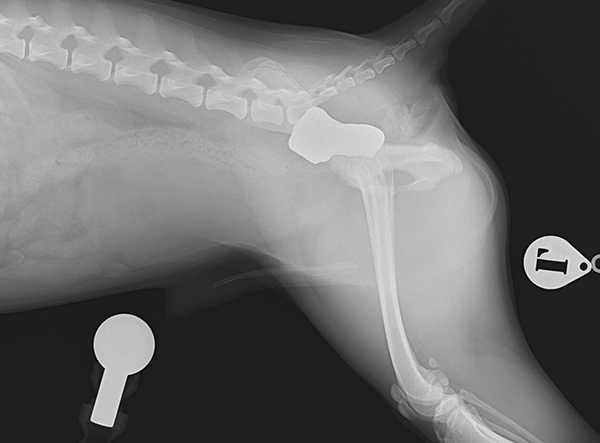

In July 2025, a tiny Shiba Inu weighing only 5.8 kg underwent a pioneering procedure for bilateral hip dysplasia — becoming one of the smallest dogs ever to receive a 3D HIP Implant Implant by Rita Leibinger.

The surgery involved implanting a 2.4 mm 3D HIP Patient-Specific Implant (Titanium) to address severe bilateral hip dysplasia. According to Prof. Dr. Björn Meij (Utrecht University), this miniature Shiba Inu represents the smallest patient on Earth to have successfully undergone this advanced orthopedic procedure. The precision and adaptability of the 3D HIP system allowed for a stable and minimally invasive intervention, tailored to the patient’s unique anatomy.

Post-operatively, the Shiba Inu is progressing well, showing encouraging signs of improved joint stability and mobility. While full rehabilitation will require time and care, the early results are highly promising, resulting in greatly reduced pain and enhanced mobility.

Implant Used: 2.4 mm 3D HIP Patient-Specific Implant – Titanium